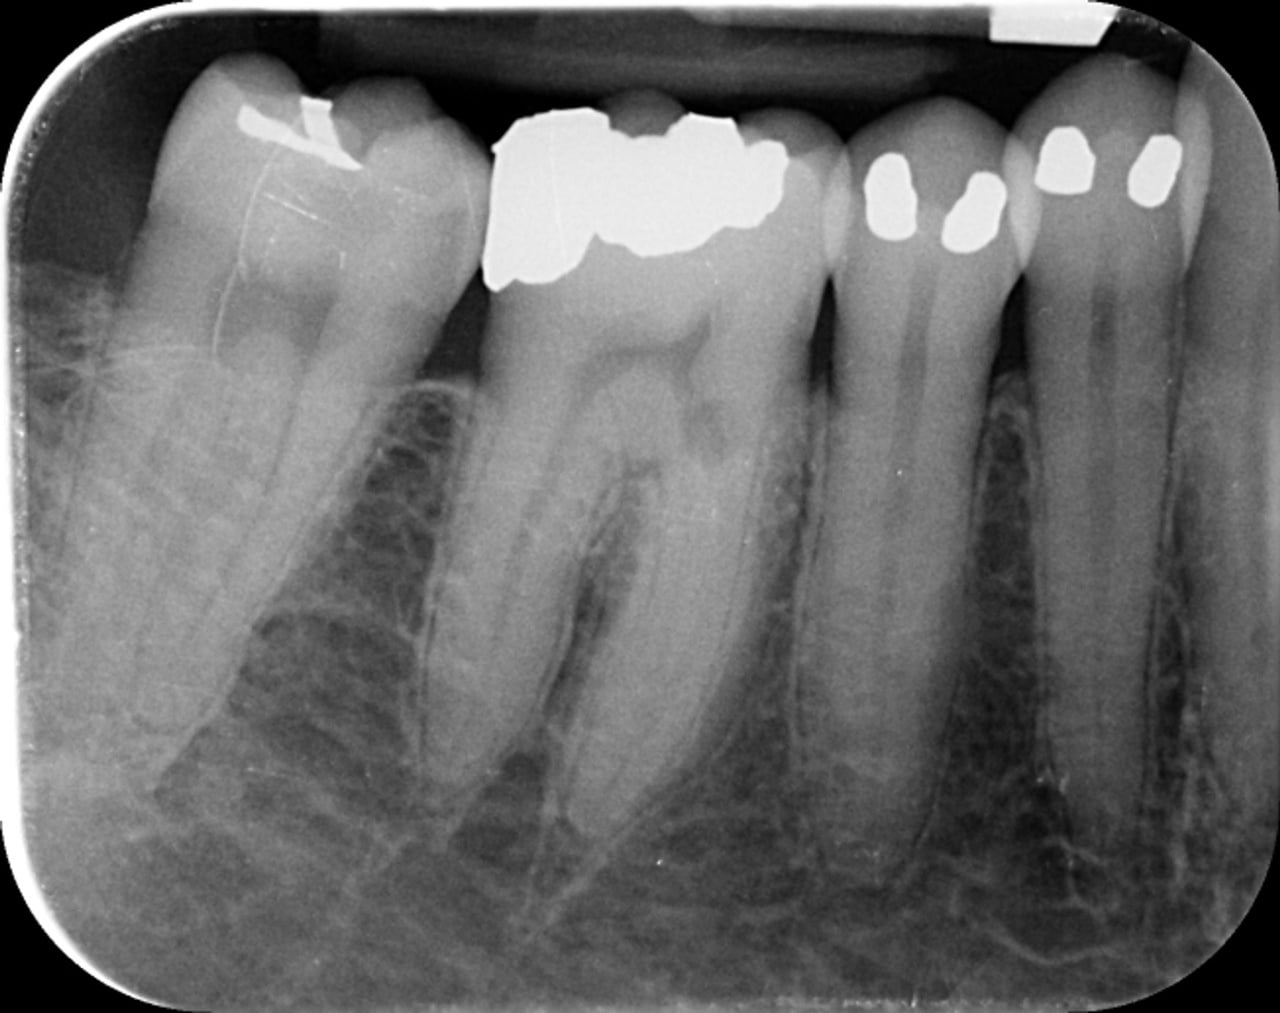

Cette lésion est clairement visible sur la radiographie préopératoire (Fig.1). Néanmoins, l’analyse de ce cliché réalisé avec un angulateur selon la technique des plans parallèles, ne permet pas de délimiter clairement les bords de cette lésion, ni d’en définir la profondeur et ses rapports avec l’endodonte de la dent concernée.

Fig.1 : Radiographie préopératoire – cliché pris selon la technique des plans parallèles avec un angulateur.